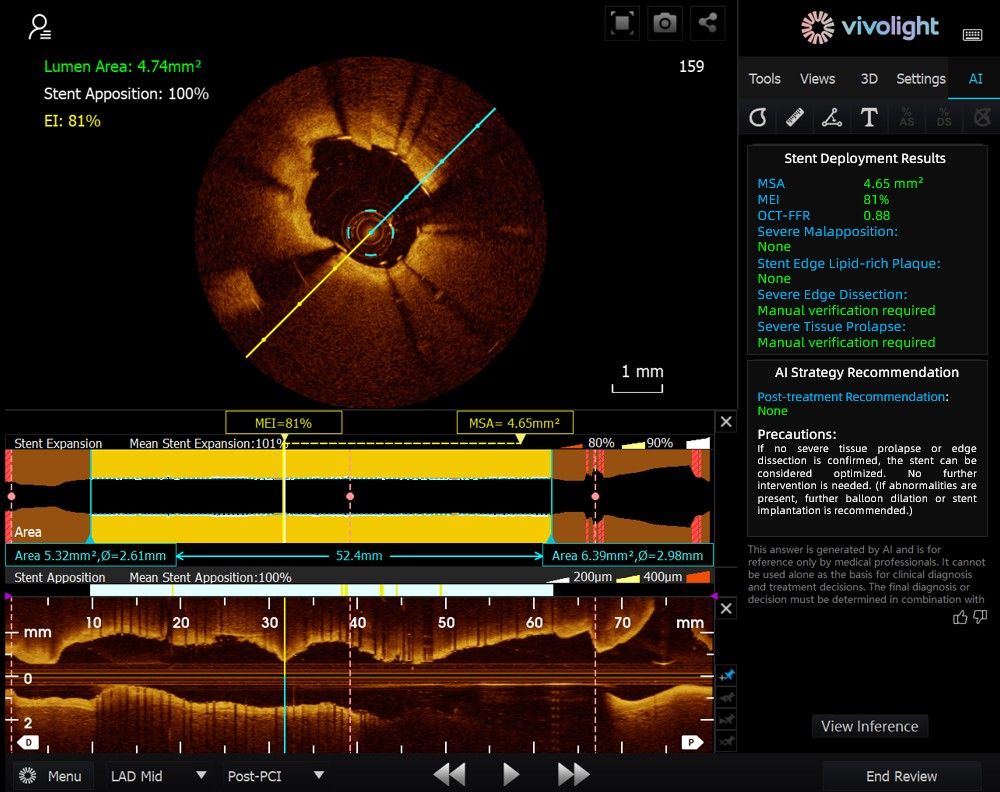

Développé à partir du système OCT de Vivolight Medical, l'AI-OCT est un système d'aide à la décision intelligent de nouvelle génération pour l'imagerie intravasculaire. Il intègre des données diagnostiques d'imagerie intravasculaire dispersées — notamment le diamètre de la lumière, les lésions responsables, l'OCT-FFR et la nature des plaques — afin d'élaborer des stratégies de traitement complètes et des recommandations concrètes. Logiciel de recherche indépendant intégré à la plateforme OCT, il est co-développé avec différents hôpitaux pour créer des versions personnalisées adaptées à des besoins cliniques spécifiques.

Lors de ce forum de pointe, les experts ont souligné que le système AI-OCT représente une transformation majeure, passant de la simple « visualisation d'images » à l'« élaboration de plans de traitement ». Il permet de relever les défis posés par la surcharge d'informations et la complexité des décisions à prendre lors des interventions cardiaques, qui reposent traditionnellement sur l'expérience du médecin. Les principaux avantages de ce système sont les suivants :

●Guidage peropératoire en temps réel : Il organise dynamiquement les informations diagnostiques pendant l'intervention chirurgicale, en fournissant des indicateurs clés et des recommandations cliniques.

Le système AI-OCT adopte une architecture « petit modèle + données massives + grand modèle » : les petits modèles permettent une interprétation précise des images, tandis que les grands modèles sous-tendent un raisonnement clinique complet. S’appuyant sur des bases de données cardiovasculaires de haute qualité et la technologie RAG (Retrieval-Augmented Generation), il offre une prise en charge globale, de l’évaluation des lésions à l’élaboration de la stratégie de traitement.